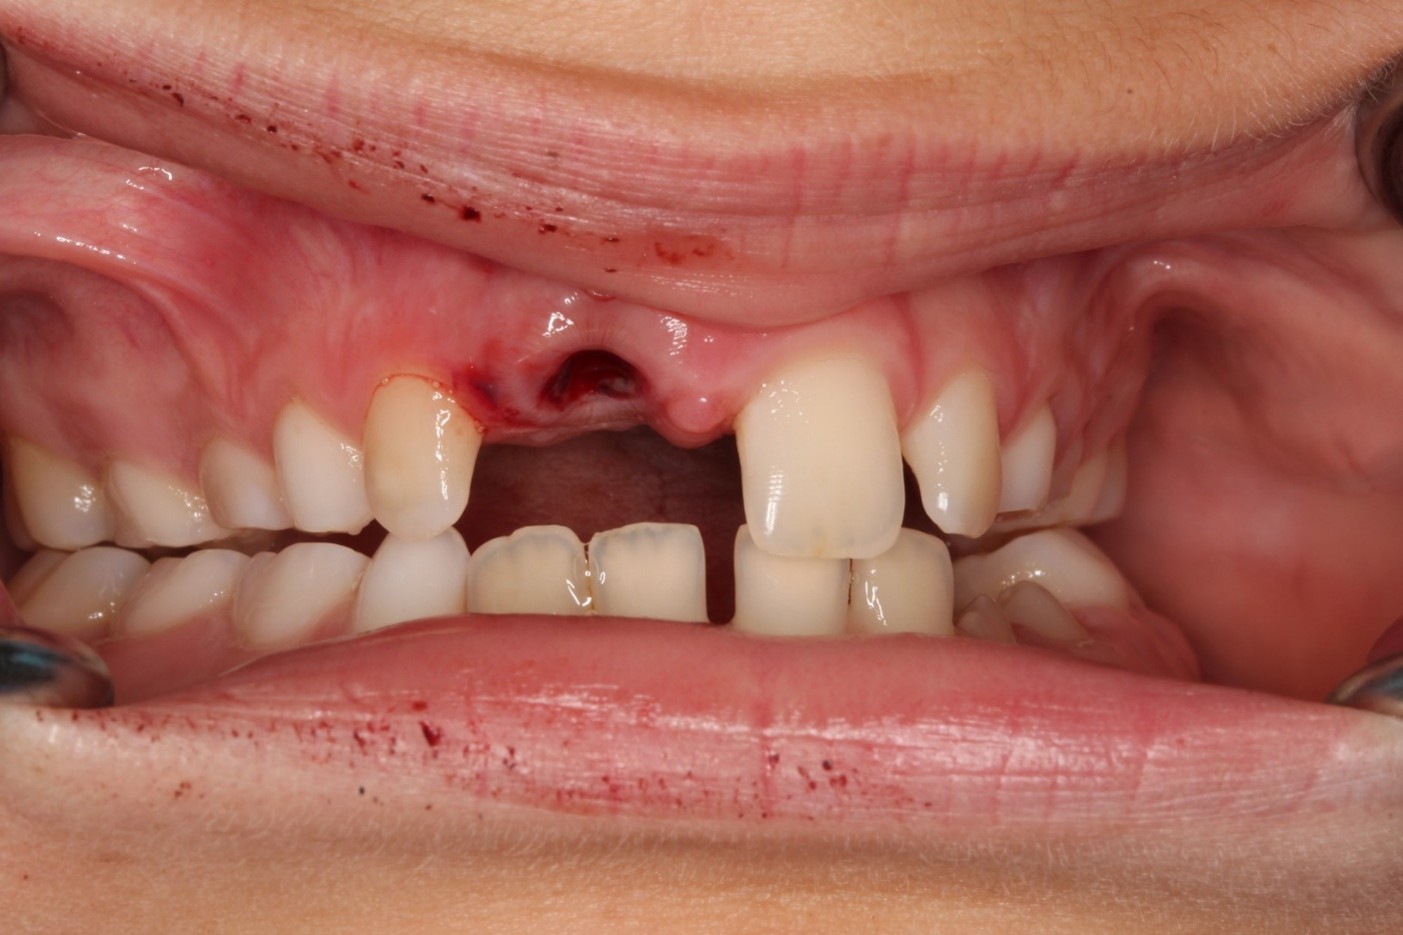

Ursachen und Therapie von Frontzahnlücken im jugendlich-bleibenden Gebiss

Ursachen für Frontzahnlücken

Fallbeispiele direkt aus der Praxis